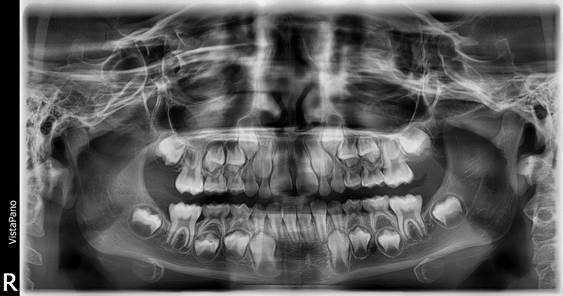

Figura 9. Análisis radiográfico

Al examen radiográfico se observa una dentición mixta.

Figura 15. Radiografía panorámica

Se observa que los incisivos laterales superiores permanentes no tienen espacio para erupcionar, por lo cual se recomienda la extracción de los caninos superiores deciduos.